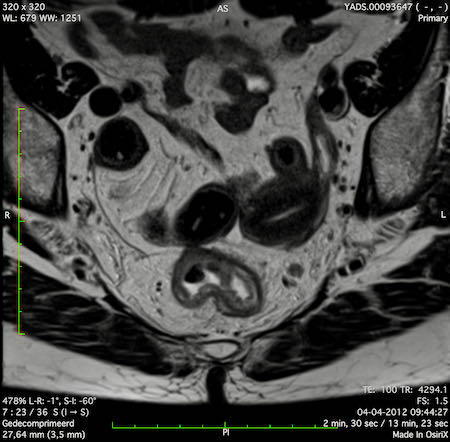

Hình ảnh

Các hình ảnh được cung cấp cho thấy ung thư biểu mô tế bào nhẫn với tình trạng dày lan tỏa thành trực tràng, hình ảnh bia bắn điển hình, và sự xâm lấn mỡ mạc treo trực tràng.